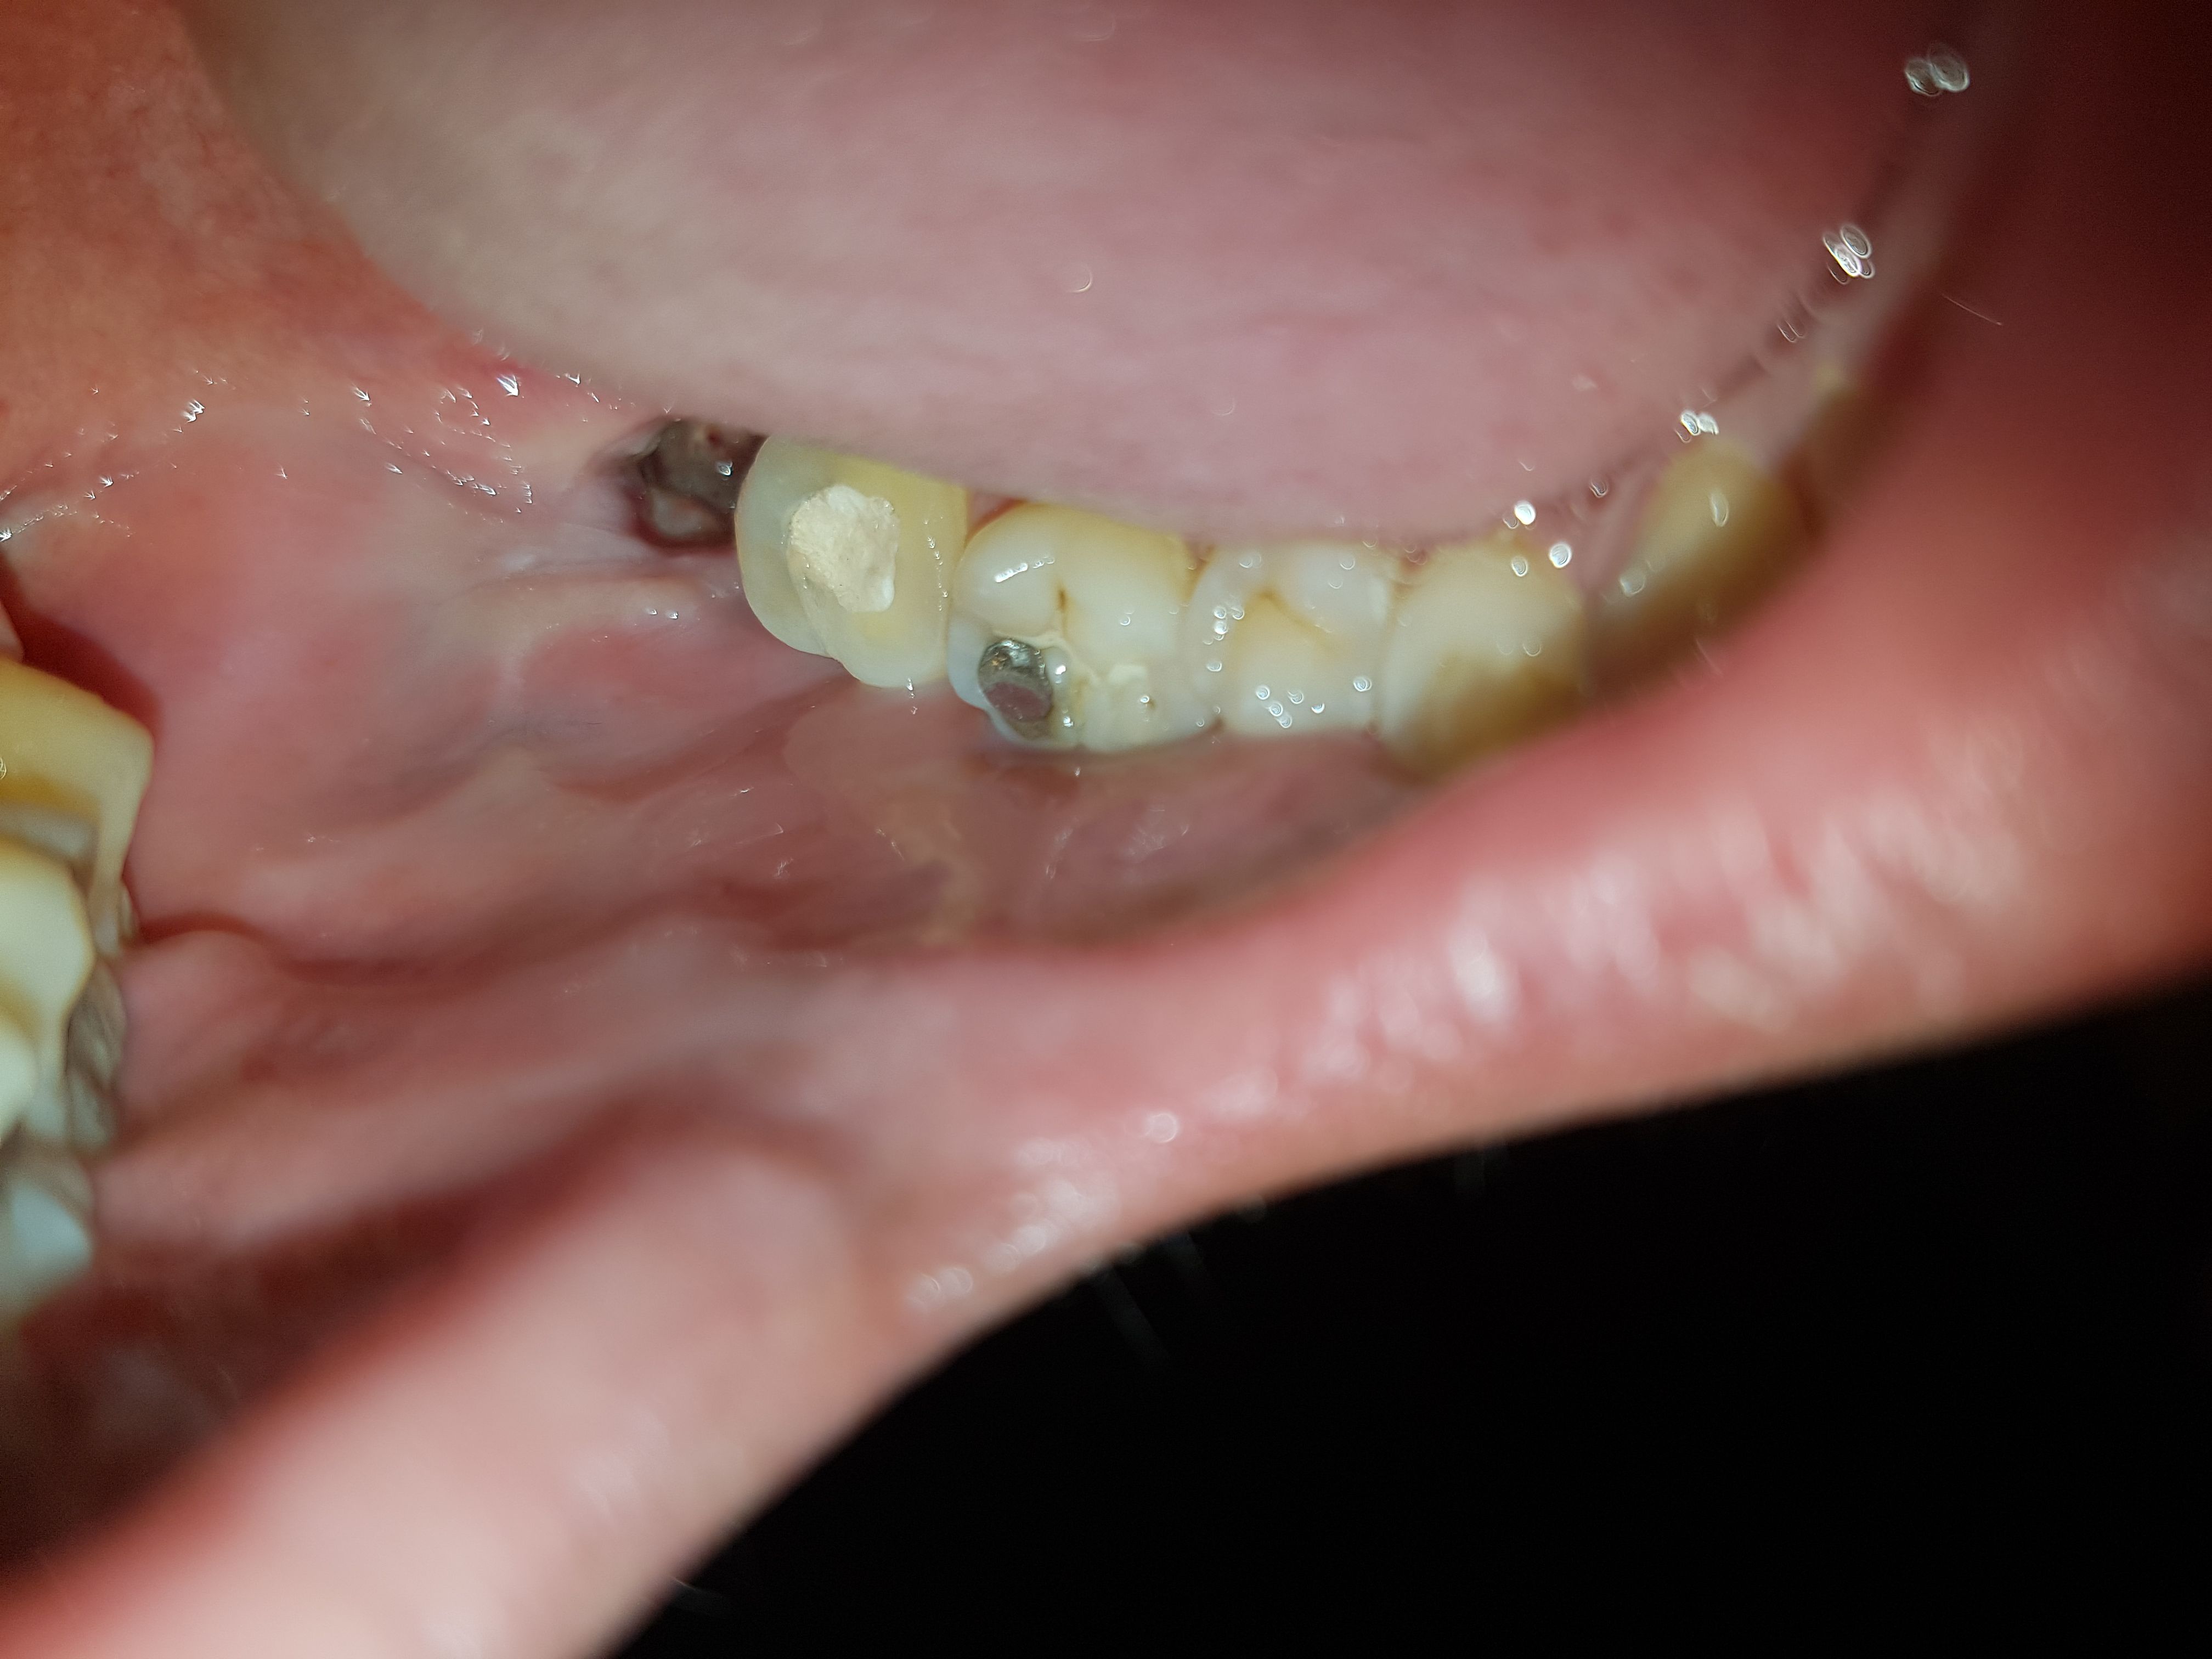

Subject   [혐주의]사랑니 원래 이런건가요?

사랑니 뺀지 일주일이 넘어가는데 아직도 욱씬욱씬 통증이 있네요..

물론 관리를 잘한건 아니지만 ...

사정상 다음주 수요일에나 치과갈수있을거 같은데 문제는 없으려나요...?